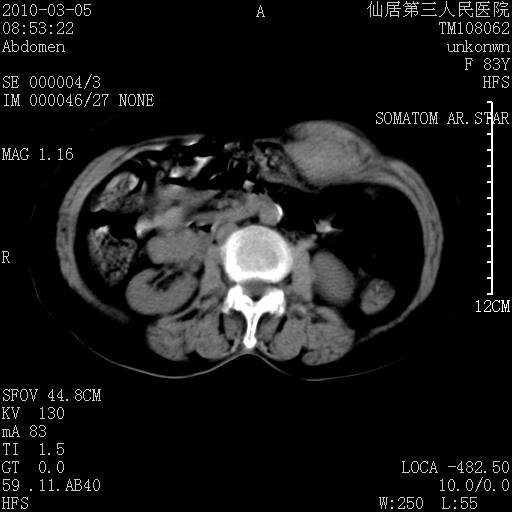

标题: CT24879:腹直肌病变。在线等。

女性,83y,腹痛一周。

考虑:左侧腹直肌神经纤维瘤可能

神经纤维瘤—伴有出血?

有无外伤,血肿或韧带样瘤

考虑左侧腹直肌血肿,肿瘤性病变待排。

增强看看,mfh可能性大,次之可考虑血肿、bfh、转移瘤、神经纤维瘤、侵袭性韧带样纤维瘤等。肝内钙化灶,右肾结石。

支持腹壁纤维肉瘤

血肿,纤维瘤,子宫内膜异位都有可能。